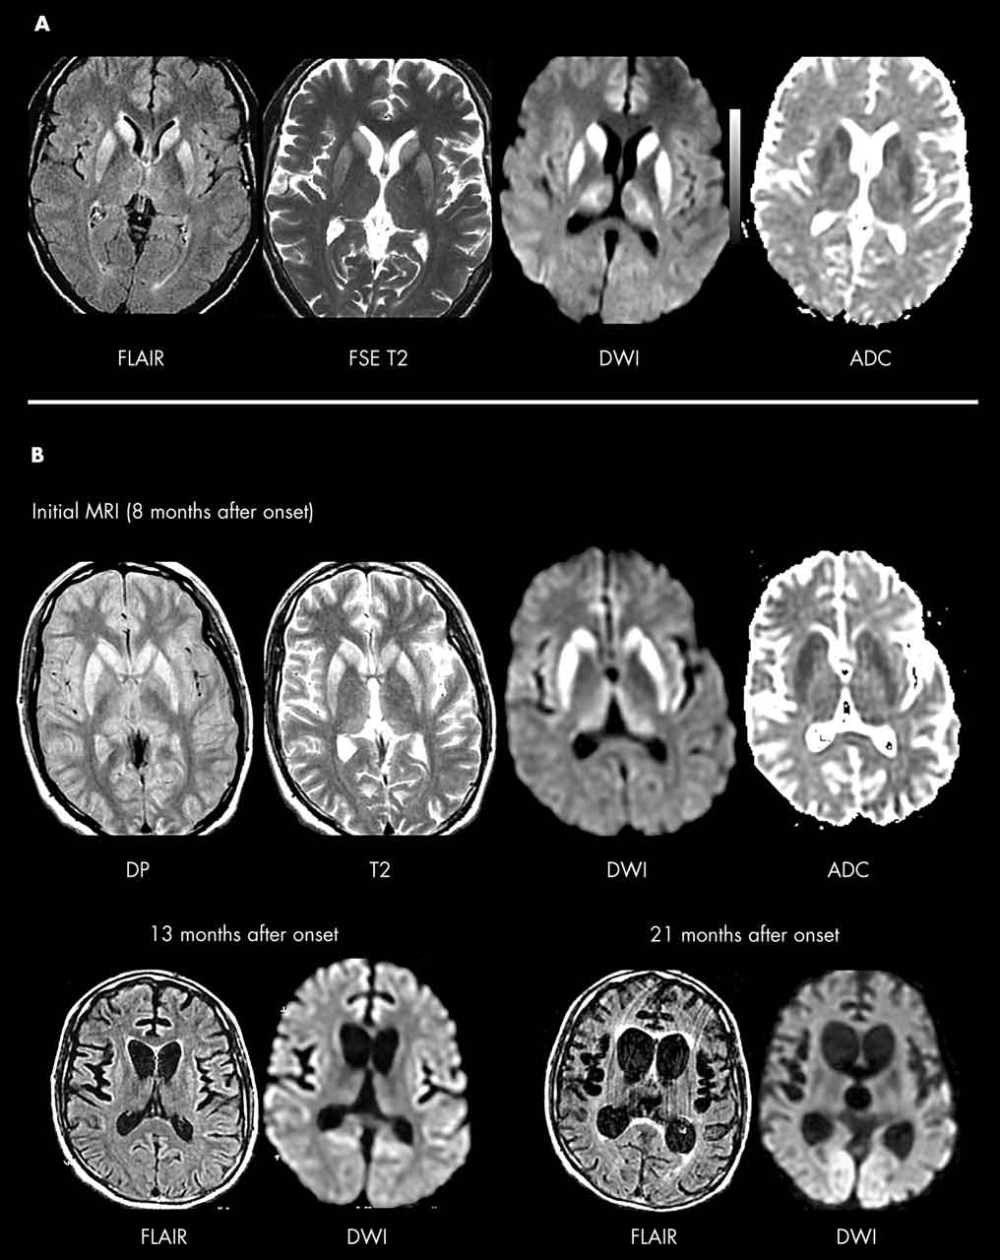

Recognizing Creutzfeldt Jakob disease symptoms

• Early symptoms include rapidly worsening memory problems, personality changes like apathy or irritability, and difficulties with balance, coordination, and walking.

• As the disease progresses, individuals may experience involuntary muscle jerks (myoclonus), blindness, weakness of the limbs, and severe mental impairment.

• The rapid decline in cognitive function and mobility is a hallmark sign, often leading to a complete loss of awareness and movement within a year.